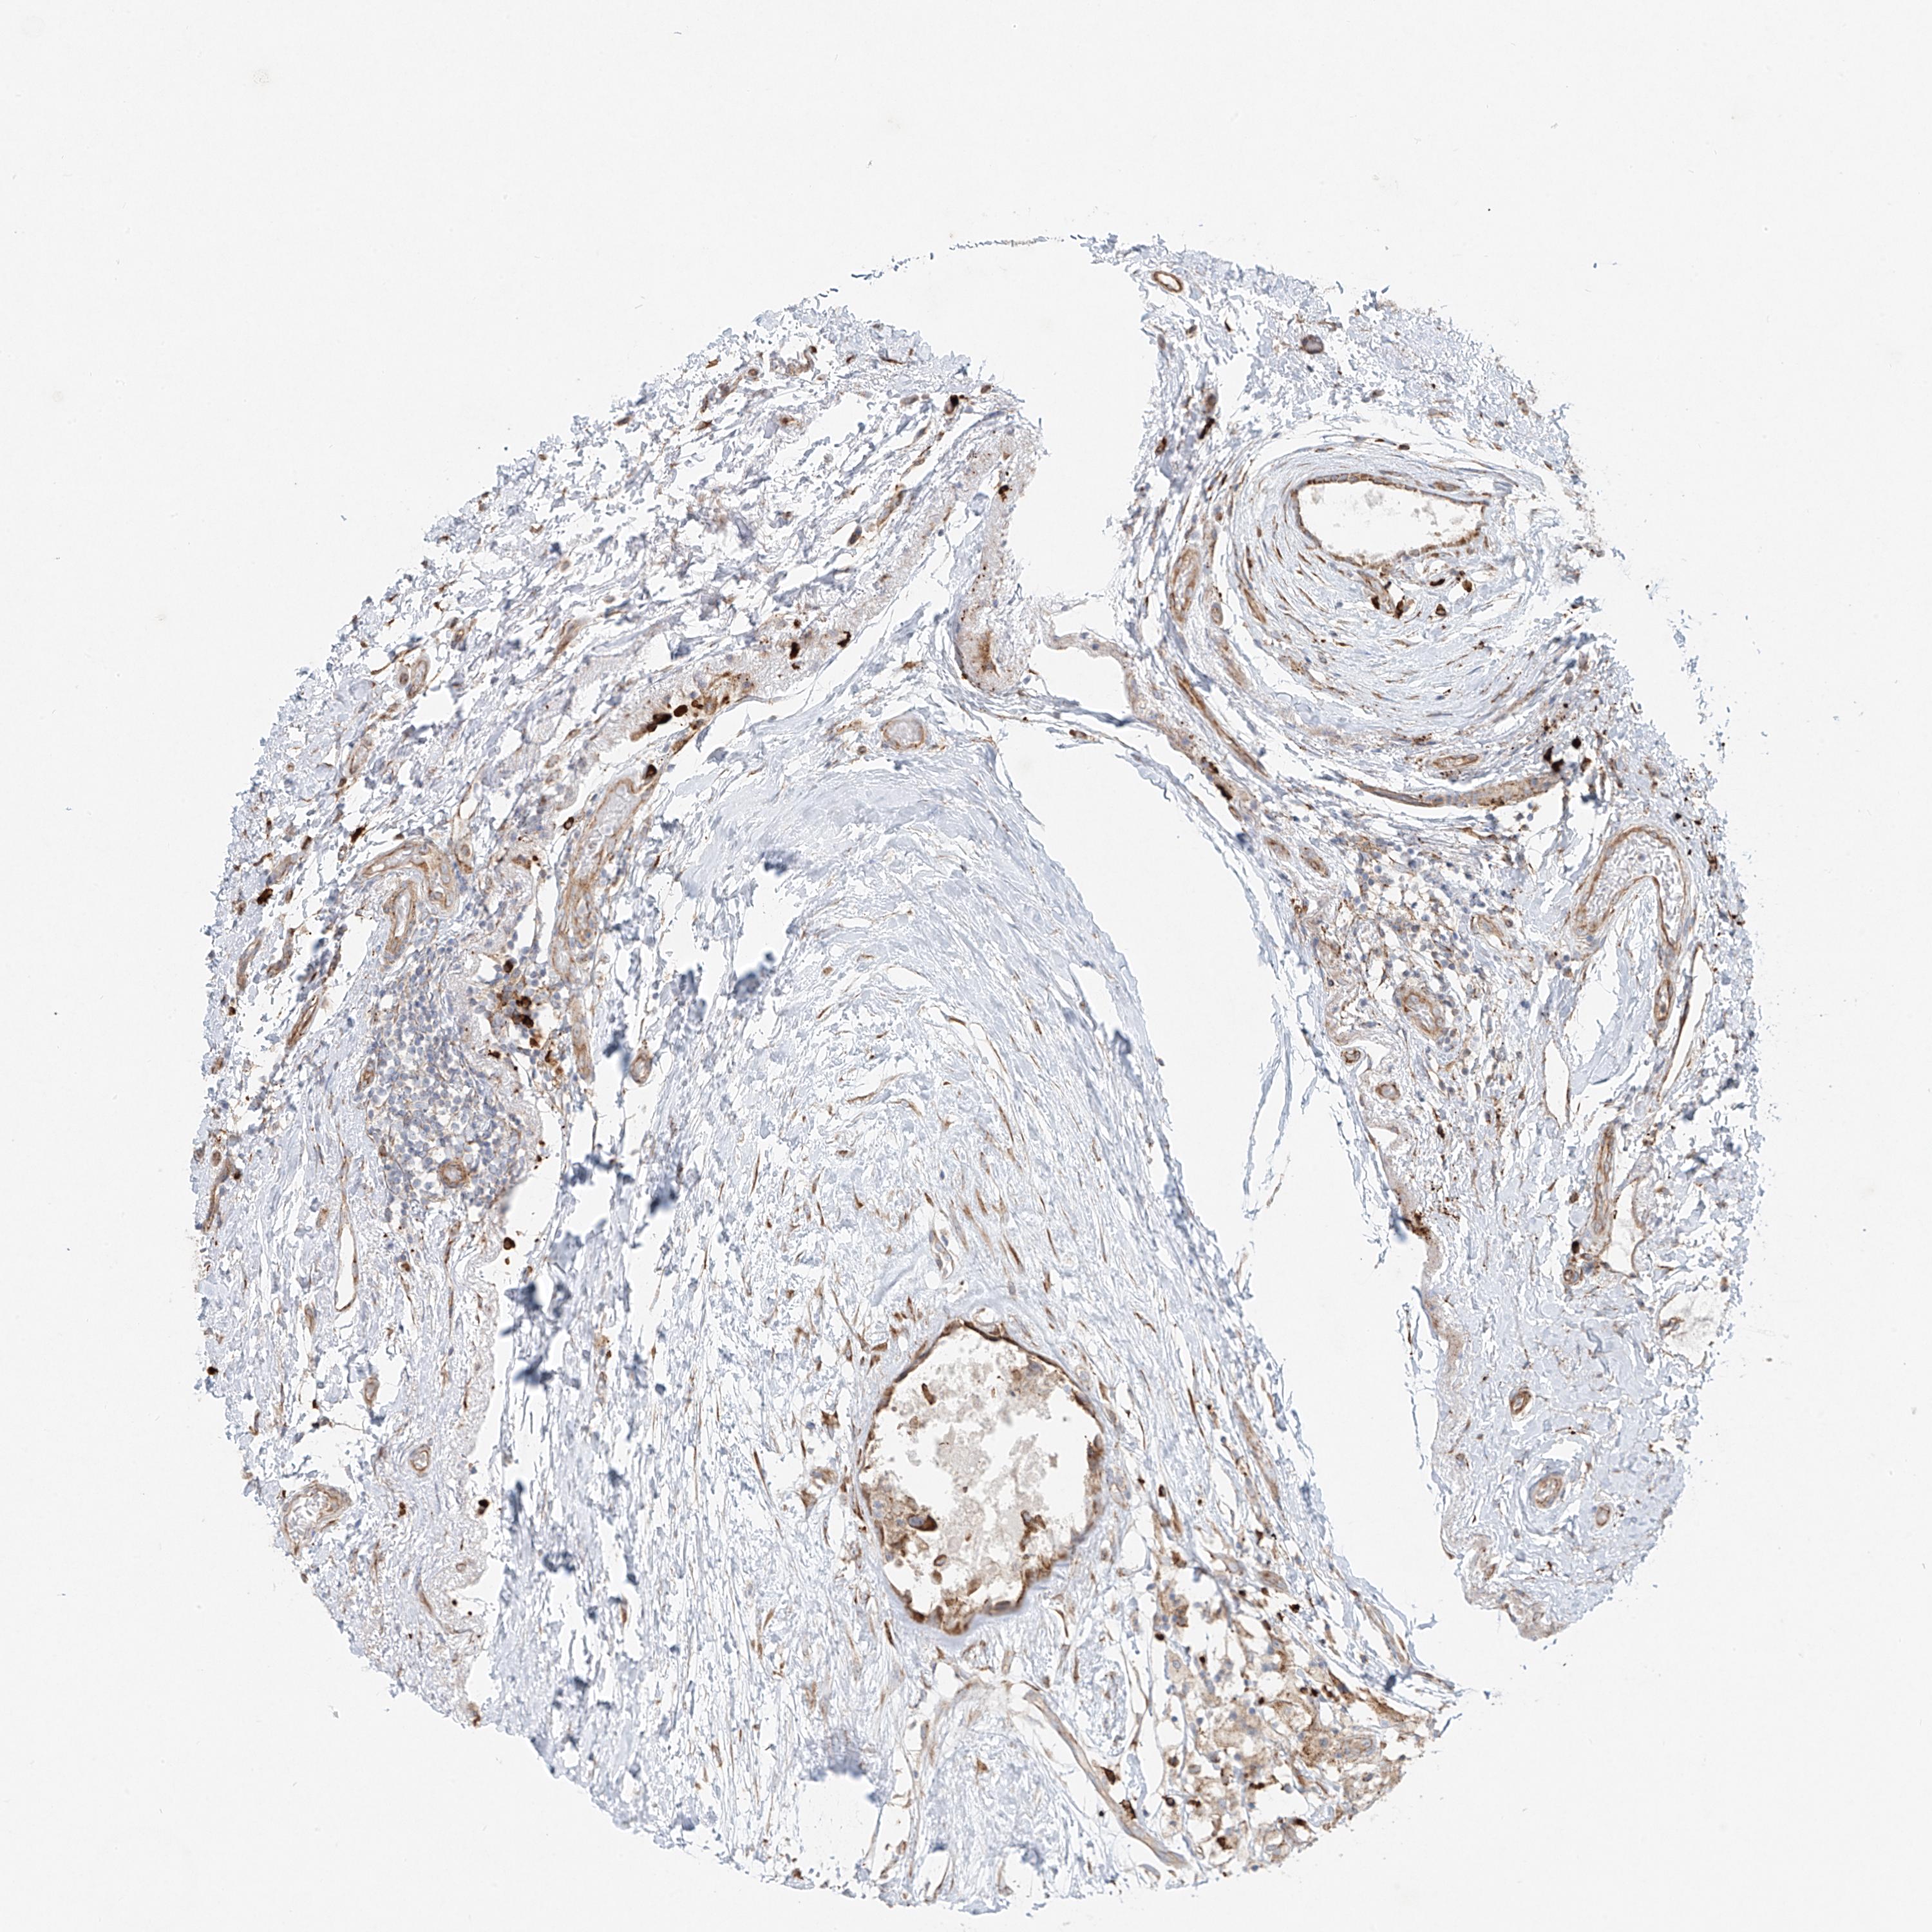

Breast cancer

Human cancer